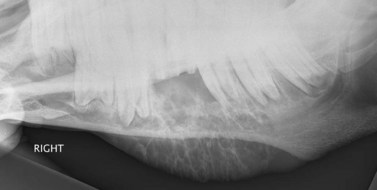

Latero35–45°ventral–laterodorsal oblique projections (Fig. 13.11)

This view is used to separate the left and right hemimandibles and mandibular cheek teeth apices in order to view the affected side without superimposition of the contralateral hemimandible. As previously noted, a higher exposure is required when imaging the caudal three cheek teeth because of the overlying thick masseter and pterygoideus muscles (Fig. 13.7). Additionally, a higher angle is usually required for radiography of the caudal cheek teeth apices because these are positioned more dorsally within the mandibular bone. For the same reason, the cheek teeth of old horses with short reserve crowns also need to be radiographed using a higher angle.

Similar to the latero30°dorsal–lateroventral oblique view, inadvertent rostrocaudal angulation of the X-ray beam is a common fault with this view of the mandible, and should be avoided, if possible, because excessive rostrocaudal angulation distorts anatomical structures, particularly the apices of the cheek teeth, making them difficult to evaluate accurately. The minimum dorsoventral angle of X-ray beam which clearly separates the left and right cheek teeth apices should be used. Using a very large oblique angle gives better separation of the cheek teeth rows and allows visualization of more reserve crown, but also causes artefactual distortion of the apices.

The standing horse should be positioned so that the lesion side is closest to the cassette, which is held in the cassette holder in a vertical plane. The primary beam should be angled 35–45° lateroventral-laterodorsal (angled up from the dorsal plane which runs parallel with the hard palate) and centered at the area of interest, such as a mandibular swelling or cutaneous discharging tract – whose presence is the usual indication for taking this radiographic view. The primary beam should be collimated to reduce scatter but should include the ventral mandibular cortex and the entire cheek teeth row, if possible.

For anesthetized horses, which are usually positioned in lateral recumbency with the affected side uppermost (to allow access for surgery), the cassette is placed beneath the horse’s head i.e., next to the unaffected side, and the direction of the X-ray beam is reversed (Fig. 13.10).